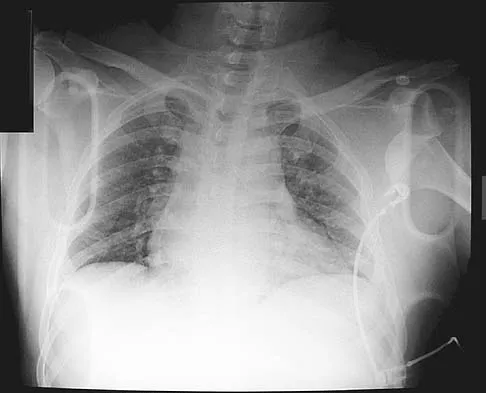

A 58-year-old woman with a history of severe asthma and long-term prednisone use reports a progression of chronic shoulder pain for the past 6 months. Radiographs and MRI scans are shown in Figures 30a through 30d. What is the most likely diagnosis?

Explanation

The patient has osteonecrosis of the humeral head. The radiographs show increased density in the superior subchondral region of the humeral head. The MRI scans reveal a central collapse of the humeral head. The patient's history of severe asthma and long-term prednisone use predisposes her to this condition. The MRI scans show no evidence of a full- or partial-thickness rotator cuff tear. Without a history of fevers, chills, or other systemic signs or symptoms, there is no indication of septic arthritis. The radiographs do not reveal periarticular erosions, commonly seen in rheumatoid arthritis. Matsen FA III, Rockwood CA Jr, Wirth MA, et al: Glenohumeral arthritis and its management, in Rockwood CA Jr, Matsen FA III (eds): Rockwood and Matsen The Shoulder, ed 2. Philadelphia, PA, WB Saunders, 1998, pp 871-874.